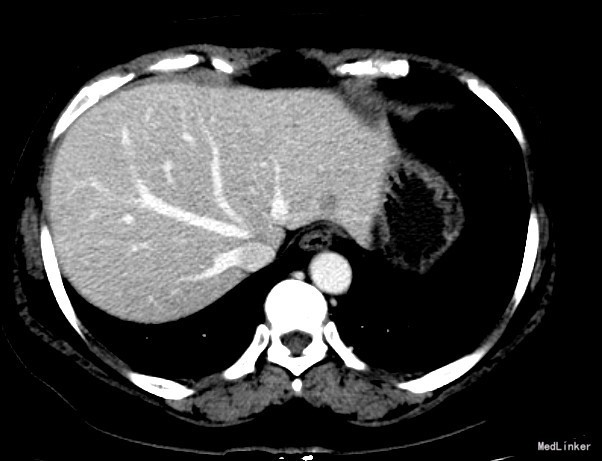

查体:体格检查:体温36.4℃,脉搏72次/分,呼吸18次/分,血压120/70毫米汞柱,神志清,状态可,皮肤及巩膜无黄染,手掌赤痕阳性,红丝赤缕阴性,心肺听诊未闻异常,腹软,无压痛,肝脾肋下未及,移动性浊音阴性,双下肢无浮肿,扑翼样震颤阴性,舌象:舌淡红、苔薄白,脉象:弦脉。 化验:血细胞分析:白细胞计数 6.3 10^9/L、红细胞计数 4.73 10^12/L、血小板计数 175.0 10^9/L、血红蛋白 156 g/L,肝功酶谱:丙氨酸氨基转移酶 22 U/L、碱性磷酸酶 84 U/L、白蛋白 43.8 g/L、总胆红素 13.3 umol/L,甲胎蛋白测定:甲胎蛋白 182.80 ng/mL 彩超:符合慢性肝损伤,肝右叶高回声性质待定0.7cm 肝弹性测定:CAP 252 E 6.9 增强CT:脾大,肝硬化?肝内多发RN,大小约1.2cm,Ⅱ段结节合并Ca变可能性大

诊断:1.乙肝肝硬化 活动性 代偿期 C-P分级 A级 5分 2.肝占位(不除外HCC) 治疗:患者乙肝肝硬化患者,多次于我院中医科住院治疗,本次住院期间中医理疗、抗病毒治疗,查甲胎蛋白增高,并且增强CT发现肝内可疑病灶,考虑原发性肝癌可能性大,于局麻下行TACE治疗,术中诊断为原发性肝癌以微导管超选S2段肝动脉一分支,造影明确为肿瘤供血动脉,注入混悬液(碘化油5毫升+雷替曲塞2毫克)3.2毫升,栓塞微球0.1毫升。

术后患者略乏力,食欲可,二便正常。 查体:神志清,状态可,皮肤及巩膜无黄染,有肝掌,无蜘蛛痣。心肺听诊未闻异常,腹软,无压痛,肝脾肋下未及,移动性浊音阴性,双下肢无浮肿,扑翼样震颤阴性。足背动脉搏动良好。 化验肝功转氨酶略有上升,甲胎蛋白下降。 DSA下肝动脉造影,即是肝癌有效的诊断手段,又是有效的治疗手段,如本例患者,在术中诊断为原发性肝癌的同时,及时进行治疗。TACE创伤小、恢复快、效果较好,是有效的治疗手段